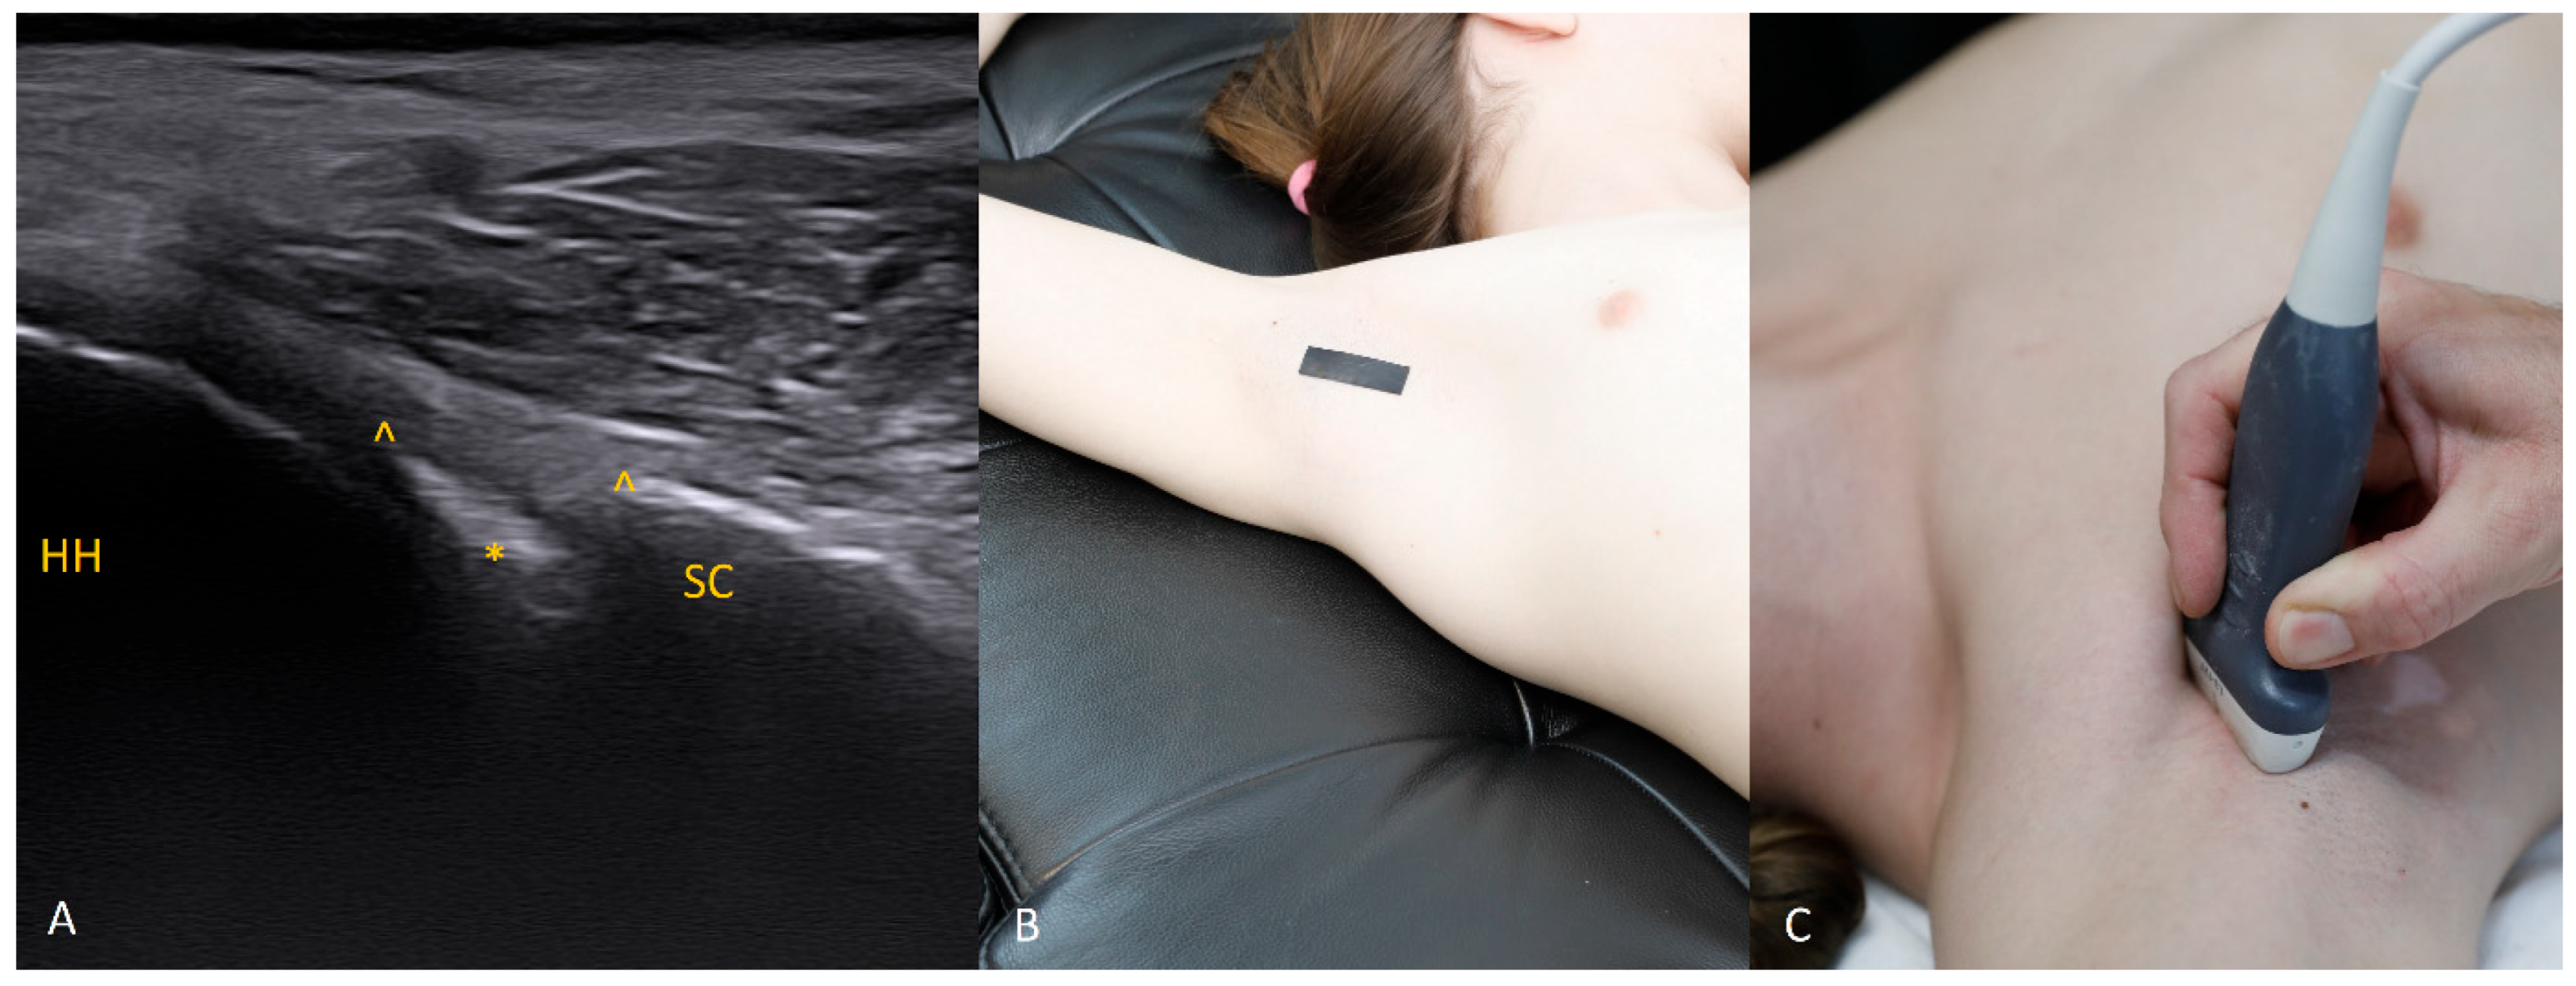

Figure 3. The 3 o’clock position. Typical transducer position and labral appearance. At 3 o’clock, if the patient has substantial muscle mass or is obese, the labrum may be examined with the patient supine. In addition to external rotation and firmer pressure on the medial transducer edge, the supine position helps compensate for the oblique orientation of the scapula relative to the chest wall. The anterior and anteroinferior labrum are the most frequent sites of injury. When looking for signs of damage, pay attention to the labral contour, the presence of fissures that may appear only during dynamic assessment (with rotation), and any medial displacement, which may be fixed (in chronic lesions) or occur only during internal rotation. In that case, during internal rotation the labrum slides medially off the glenoid rim, whereas with external rotation it returns to its proper position (reduction) under tension from the glenohumeral ligaments [8,9,10].